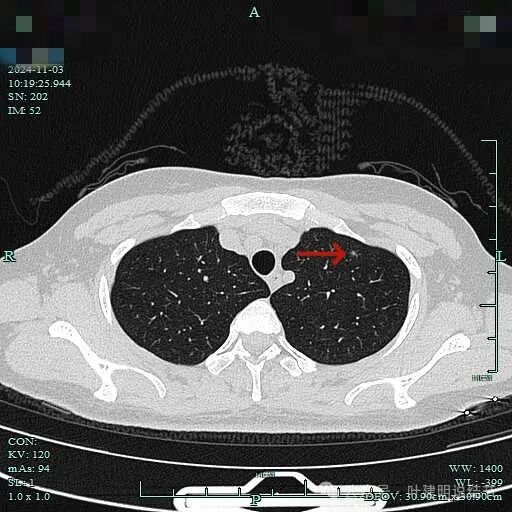

2、影像展示与分析:

薄层上病灶出现,点状,边缘不光滑。